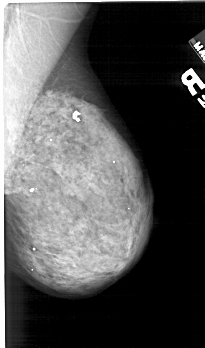

A_1420_1.RIGHT_MLO

RIGHT_MLO LINES 5206 PIXELS_PER_LINE 3061 BITS_PER_PIXEL 12 RESOLUTION 43.5 NON_OVERLAY